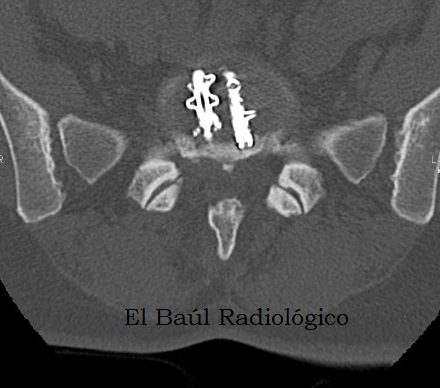

La mayoría de estos objetos están fabricados en titanio, material no ferromagnético, que no supone ningún peligro para las personas que se van a someter a una exploración de Tomografía por Resonancia Magnética (TRM). Sí, en cambio, provocan la aparición de artefactos por susceptibilidad magnética que impiden la correcta evaluación de la zona quirúrgica, lo cual supone un inconveniente. Cuando el material utilizado es de acero, los artefactos que aparecen son mayores. En este caso no hay que temer por las posible consecuencias porque es imposible que los tornillos de la artrodesis, correctamente insertados, sean removidos por la fuerza del campo magnético del imán. Otro efecto indeseable es el calentamiento del metal que se puede producir, cuando se realizan exploraciones muy largas. Hay que tenerlo en cuenta y ser resolutivos. Con dos o tres secuencias es suficiente para realizar un examen de TRM cervical.

(Most surgical devices in use today are made from titanium, non-ferromagnetic material, which poses no danger to people who are about to undergo a MRI exam. They provoke the appearance of magnetic susceptibility artifacts that prevent us the proper evaluation of the surgical site. When the material used is steel, the artifacts are greater. In this case it is impossible that arthrodesis screws are removed by the magnetic field strength of the magnet. Another effect indeseable is heating the metal, when scans are very long. This should be taken into account. With two or three sequences is enough to made an examination of TRM).

Los dispositivos más raros y variados que se suelen encontrar en cualquier imagen radiográfica, son los que utilizan los traumatólogos y neurocirujanos para estabilizar las vértebras de la columna lumbar. Como son de titanio no suelen contraindicar ninguna exploración de TRM. Tampoco se calientan, ni se mueven. En cambio, en los exámenes de TC producen numerosos artefactos radiales, como cualquier otro metal.

(The most rare and varied devices that we usually find are those used by orthopedic surgeons and neurosurgeons, to stabilize the vertebrae of the lumbar spine. Here are some very specific models of interspinous metal implants used in our hospital. Made of titanium, they not contraindicate any exploration of MRI. Neither heat, nor moved. In contrast, in CT examinations they produce many radial artifacts, like any other metal)

artrodesis.png

FIGURA 2) Proyección anteroposterior magnificada de la columna cervical y de la placa de artrodesis.